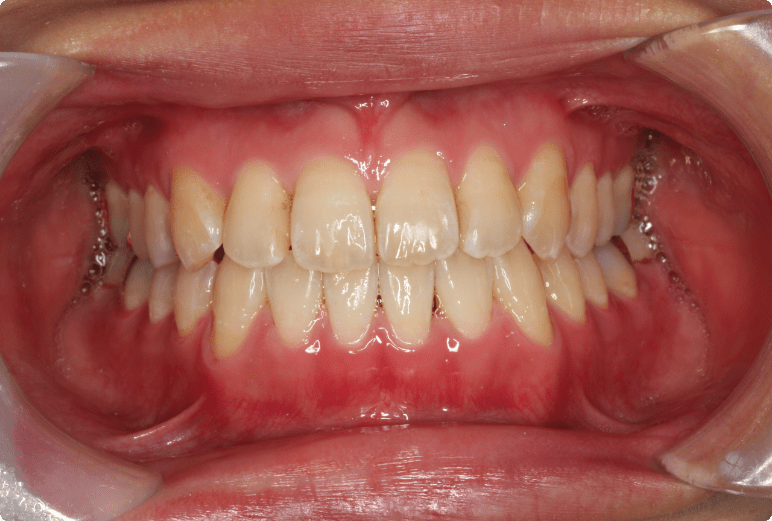

出っ歯を矯正治療で改善した症例

BEFORE

AFTER

症例概要

年代、性別

20代 女性

主訴

出っ歯

診断

骨格性Ⅰ級、歯性Ⅰ級、上顎前突

治療内容

下顎左右4番抜歯(4本)、唇側ワイヤー矯正、リテーナー

治療期間

約2.5年+メンテナンス

治療リスク

痛み、歯根吸収、歯肉退縮、ブラックトライアングル

治療費用

1,100,000円(税込)